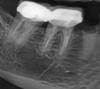

bilal Опубликовано 12 июня, 2013 Поделиться Опубликовано 12 июня, 2013 (изменено) Помогите советом.Пациентка около 50 лет, пришла на удаление корня 45. Но после рентгена обнаружил диструкцию в области корней 46, 47. Жалоб никаких нет, перкусия отрицательная, пальпация в области диструкции отрицательная. Объяснил пациентке ситуацию и прогноз, и решили попробовать перелечить оба зуба. Начал с 46. Пациентка в курсе о возможном неуспешном лечении при таком дефекте и о риске удаления.Вопрос: Если прийдется удалить, то какой? я думаю, что это от 46. Как вы думаете? Или может это вообще не связано с зубами (периодонтальная щель прослеживается). Изменено 12 июня, 2013 пользователем bilal Ссылка на комментарий

kriokov Опубликовано 12 июня, 2013 Поделиться Опубликовано 12 июня, 2013 дайте нормальный снимок.это (образование) может не иметь отношения к зубу.снимок плохой и маленький.+1, ОПТГ и КЛКТ этой зоны, на маленьком снимке видно , что периодонтальная щель везде прослеживается, а "очаг" не связан с зубами. Это может быть и просто структура костной ткани так выражена в этой зоне. 3 Ссылка на комментарий

kriokov Опубликовано 12 июня, 2013 Поделиться Опубликовано 12 июня, 2013 не уверен, что структура кости. Красная стрелка- похоже на деструктивный очаг округлой формы, синяя как бы- кортикалка, зеленая - как бы второй очаг.Наверное перелечивать оба, и потом все таки КЛКТ, если нет то ОПТГ повторно. Ссылка на комментарий